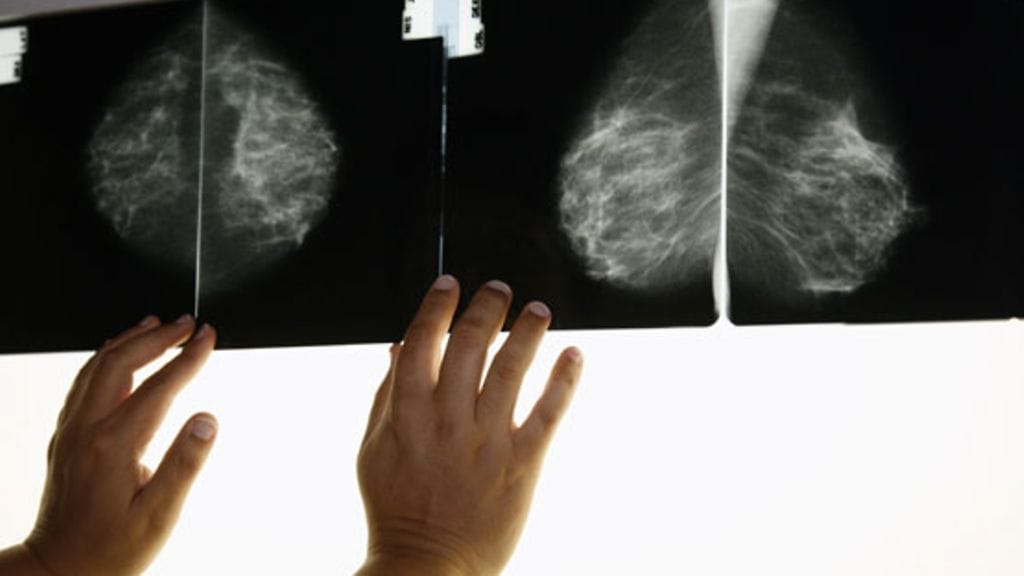

Suomessa seulotaan kaikki 50–70-vuotiaat naiset. Mammografia ja ultraäänikuvaukset paljastavat jo sellaisetkin alkuvaiheen muutokset, joita ei omin silmin tai käsin voi huomata.

– Seulonnoissa löydetään jopa 3–5 millimetrin kokoiset muutokset. Syöpä voi tosin ilmaantua myös seulontojen välisenä aikana, jos se on nopeasti kasvavaa laatua tai ollut edellisessä tarkastuksessa vielä liian alussa havaittavaksi.